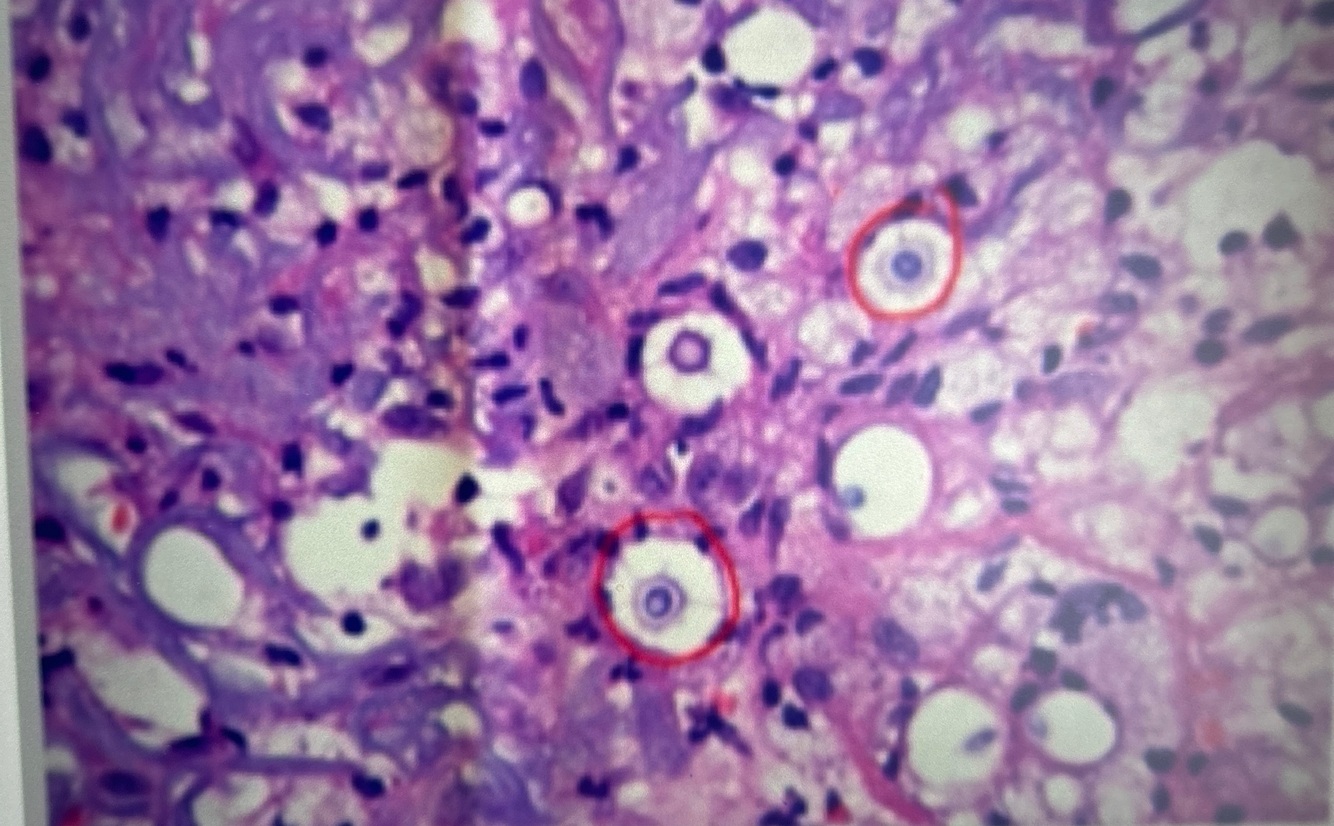

Qual diagnóstico?

Criptococose

Leveduras capsuladas